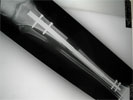

Post Op

Intramedullary bone lengthening using Fitbone nail to correct 5cm tibia shortening

Follow Up

Regenerate formed at distraction site with length correction and plantigrade foot